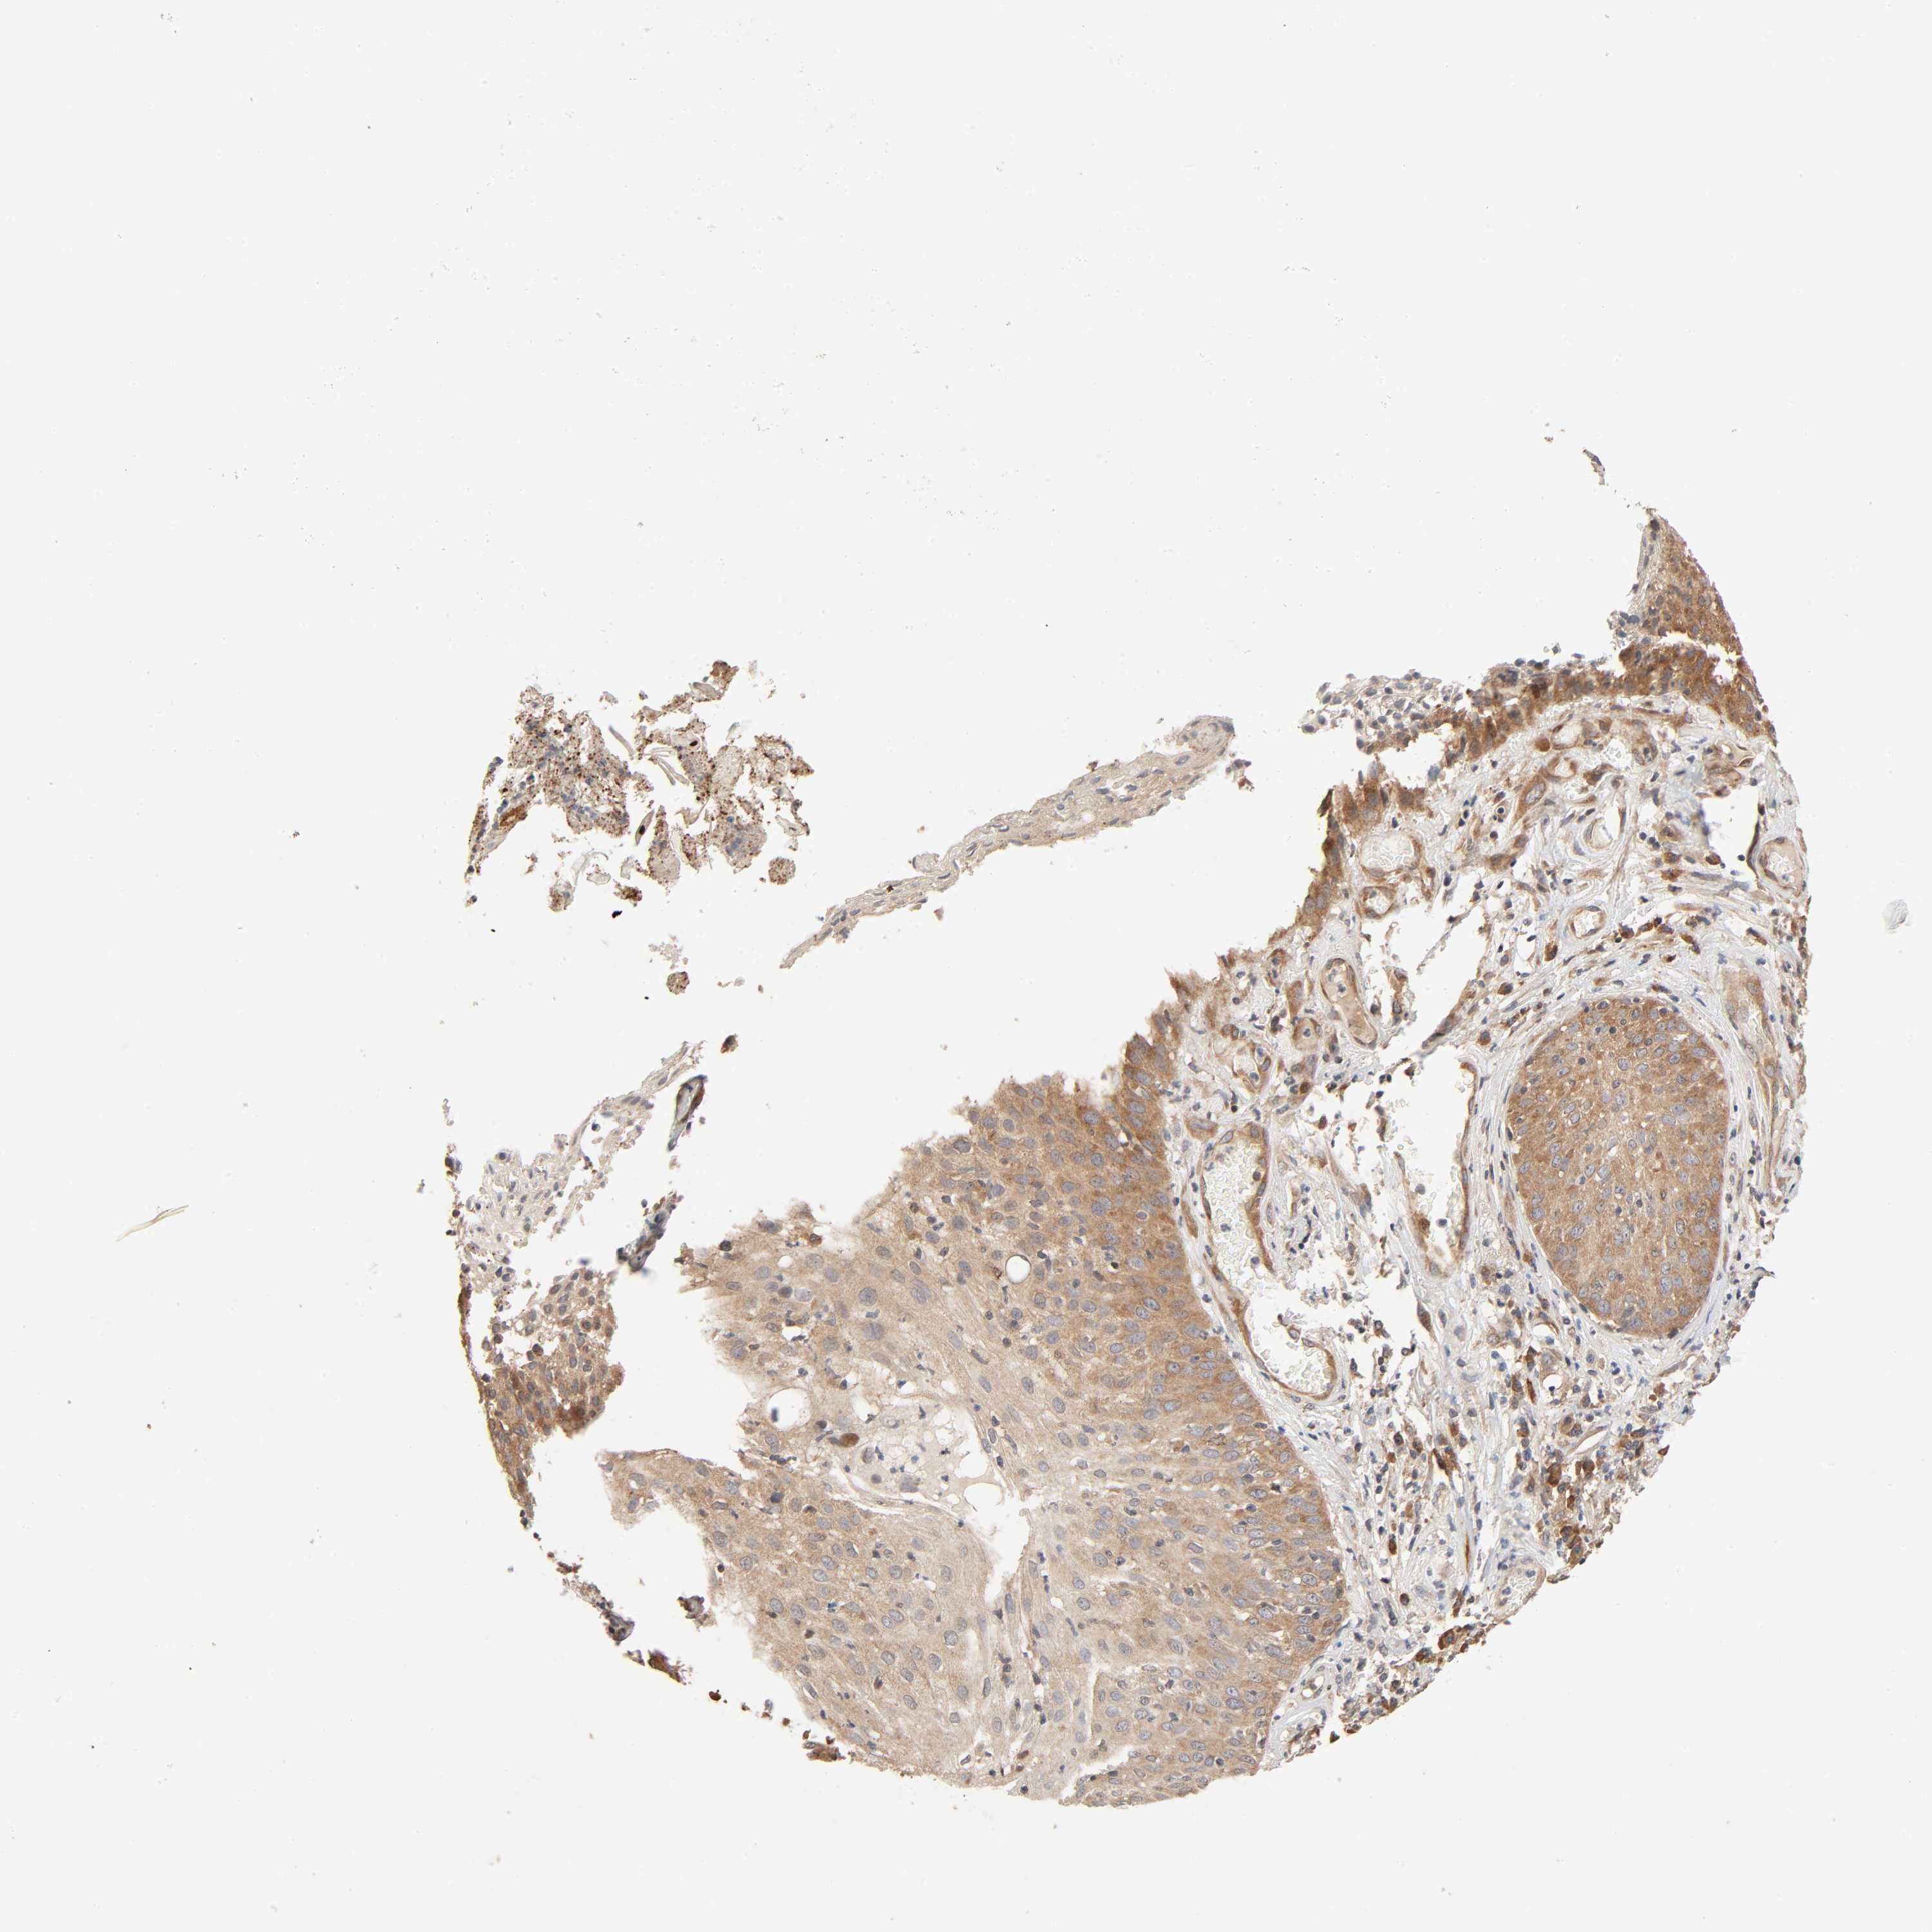

Basal cell and squamous cell cancer

SKIN CANCER - Protein expressioni

A mouse-over function shows sample information and annotation data. Click on an image to view it in a full screen mode. Samples can be filtered based on level of antibody staining by selecting one or several of the following categories: high, medium, low and not detected. The assay and annotation is described here.

Antibody stainingi

Antibody staining in the annotated cell types in the current human tissue is reported as not detected, low, medium, or high, based on conventional immunohistochemistry profiling in selected tissues. This score is based on the combination of the staining intensity and fraction of stained cells.

Each image is clickable and will lead to virtual microscopy that enables deeper exploration of all samples and also displays staining intensity scores, fraction scores and subcellular localization as well as patient and tissue information for each sample.

Antibody HPA004160

Staining

High

Medium

Low

Not detected

Intensity

Strong

Moderate

Weak

Negative

Quantity

>75%

75%-25%

<25%

None

Location

Nuclear

Cytoplasmic/membranous

Cytoplasmic/membranous,nuclear

Squamous cell carcinoma, NOS

Basal cell carcinoma